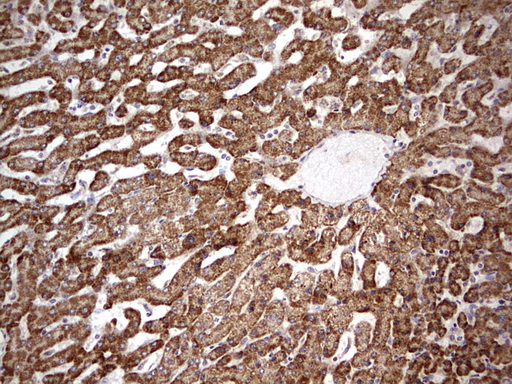

Immunohistochemical staining of paraffin-embedded Human liver tissue within the normal limits using anti-APC mouse monoclonal antibody. (M00008-2; heat-induced epitope retrieval by 1mM EDTA in 10mM Tris, pH8.5, 120°C for 3min)

Immunohistochemical staining of paraffin-embedded Human liver tissue within the normal limits using anti-APC mouse monoclonal antibody. (M00008-2; heat-induced epitope retrieval by 1mM EDTA in 10mM Tris, pH8.5, 120°C for 3min)